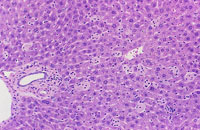

Kupffer cell hyperplasia and hypertrophy is rarely seen in mice. Hypertrophic Kupffer cells may contain pigment in some cases.

Examples of Kupffer cell hyperplasia.